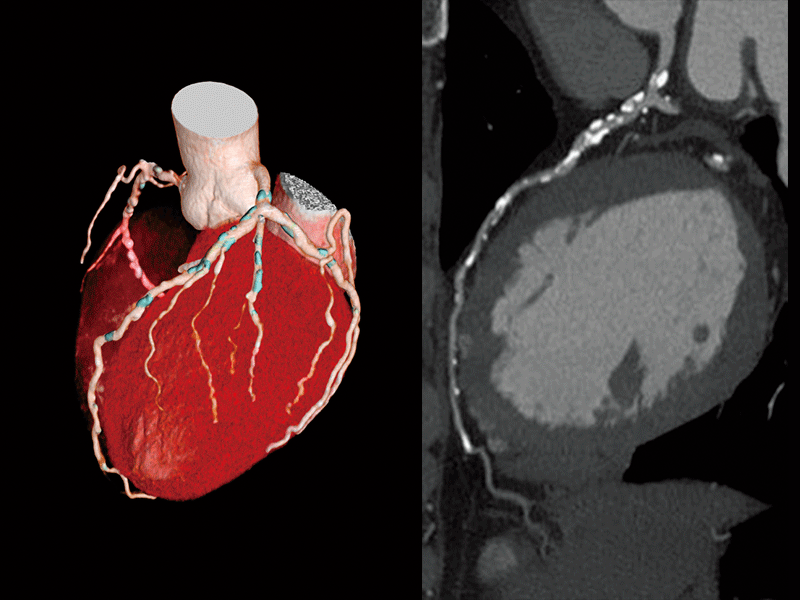

Coronary artery calcifification

Follow-up after CABG

Follow-up after LAD stenting